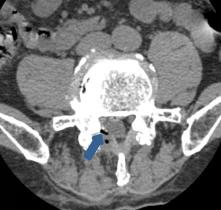

• 单纯内镜乳头小球囊扩张术在胆总管较大结石中的应用效果及安全性

2025, 31(12):56-63. DOI: 10.12235/E20250208

摘要 (70) HTML (39) PDF 743.90 K (64) 评论 (0) 收藏

摘要:目的 分析内镜乳头小球囊扩张术(EPSBD)治疗胆总管较大结石(直径10~15 mm)的临床效果及安全性。方法 选择2020年1月-2023年12月该院收治的胆总管较大结石(直径10~15 mm)患者142例,采用随机数表法分为观察组与对照组,各71例。观察组行EPSBD(扩张球囊直径10 mm)治疗,对照组行内镜十二指肠乳头括约肌切开术(EST)联合球囊扩张术(EPBD)治疗。比较两组患者围手术期相关指标(取石成功率、取石时间、术后首次排便时间和住院时间),术前和术后48 h肝功能指标[总胆红素(TBiL)、谷丙转氨酶(GPT)和谷草转氨酶(GOT)],术后早期与远期并发症的发生情况,以及术后12个月内实施腹腔镜胆囊切除术(LC)情况。结果 两组患者取石成功率、取石时间、术后首次排便时间和住院时间比较,差异均无统计学意义(P > 0.05);术后48 h,两组患者血清TBiL、GPT和GOT水平明显低于术前,差异均有统计学意义(P < 0.05),但两组间比较,差异均无统计学意义(P > 0.05);观察组术后早期并发症发生率为11.27%,与对照组的8.45%比较,差异无统计学意义(P > 0.05);观察组术后远期并发症发生率为2.82%,明显低于对照组的16.90%,差异有统计学意义(P < 0.05);术后12个月内,观察组有5例实施了LC,对照组有4例实施了LC,两组间比较,差异无统计学意义(P > 0.05)。结论 应用EPSBD治疗胆总管较大结石(10~15 mm),与EST + EPBD治疗方案相比,能获得相近的取石成功率,但前者有利于降低远期并发症的发生率。值得临床推广应用。